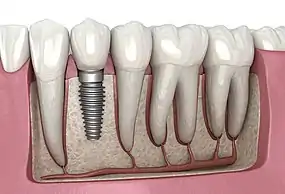

Dental Implant

Dental Implant, 3D Illustration

A dental implant (also known as an endosseous implant or fixture) is a prosthesis that interfaces with the bone of the jaw or skull to support a dental prosthesis such as a crown, bridge, denture, or facial prosthesis or to act as an orthodontic anchor. The basis for modern dental implants is a biological process called osseointegration, in which materials such as titanium or zirconia form an intimate bond to the bone. The implant fixture is first placed so that it is likely to osseointegrate, then a dental prosthetic is added. A variable amount of healing time is required for osseointegration before either the dental prosthetic (a tooth, bridge, or denture) is attached to the implant or an abutment is placed which will hold a dental prosthetic/crown.